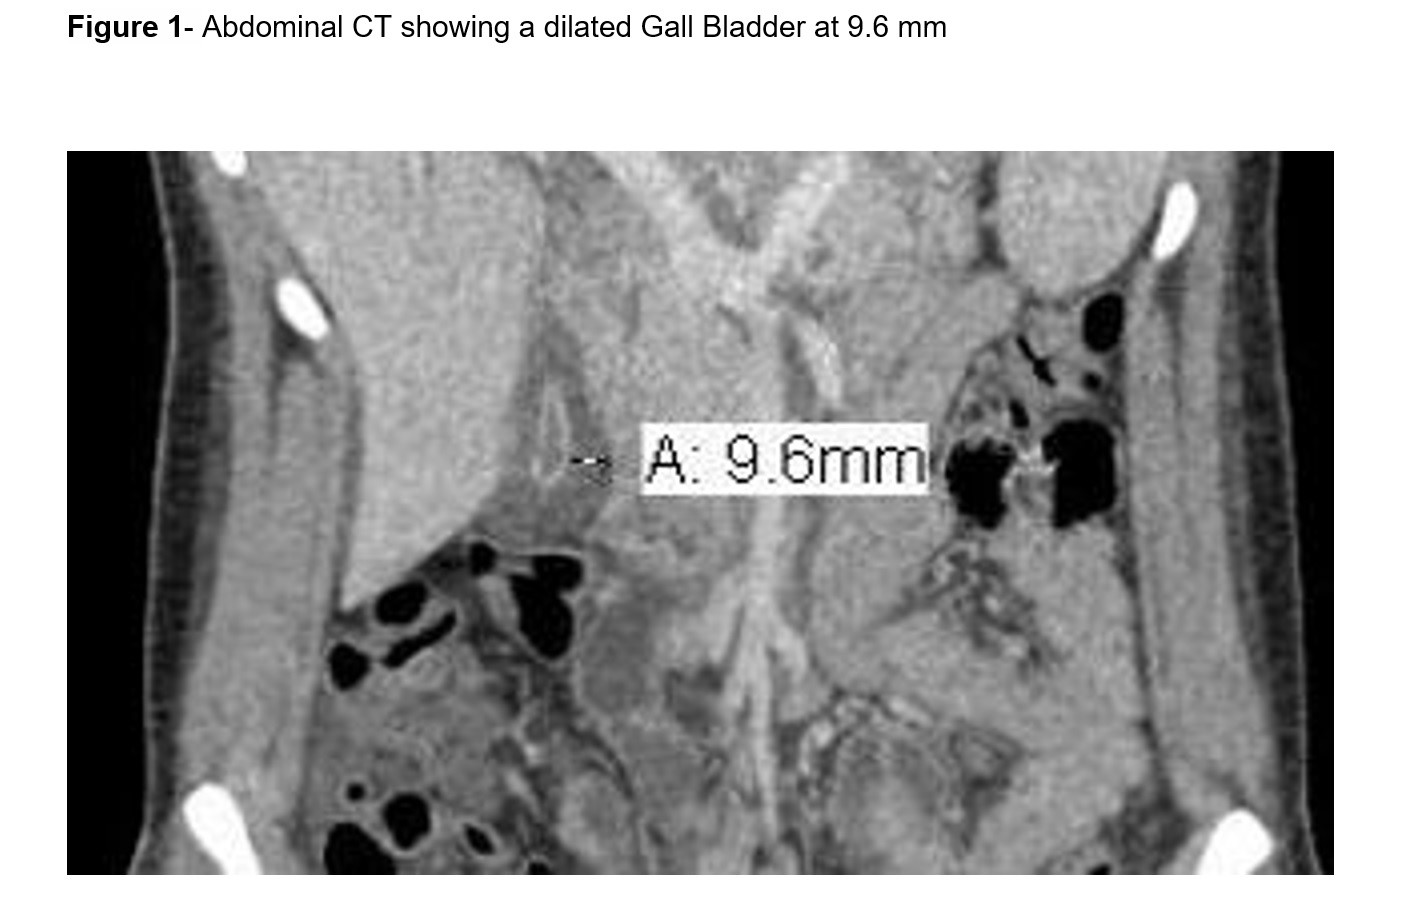

Case Presentation: An 18 years old female with no significant medical history was initially admitted to an outside hospital for urinary tract infection with sepsis. She subsequently developed abdominal pain and elevated liver enzymes prompting transfer to our institution. Physical examination consistent with right upper quadrant pain but remainder was unremarkable. Laboratory testing revealed a total bilirubin 6 mg/dl, Alk phosp 262 U/L, AST 429 U/L, ALT 305 U/L, and WBC 11.5 per microliter. CT showed a 9.6 mm gallbladder wall thickening, and pericholecystic fluid (Figure 1). HIDA scan showed a patent biliary system and endoscopic ultrasound showed no evidence of stone or sludge. HIV, RPR, Chlamydia-Gonorrhea, Hepatitis panel, CMV, ANA, AMA, and ASMA were negative. Immunoglobulins, iron profile, and ceruloplasmin levels were normal. Ebstein-Barr Virus (EBV) PCR was positive at 1384 copies/ml so acalculous cholecystitis (ACC) secondary to EBV infection was felt to be the likely diagnosis. Surgery was consulted and advised for conservative management. She clinically improved and was discharged home.

The etiology and pathogenesis of ACC remains uncertain. Abdominal US is considered as an effective tool to confirm diagnosis. In our patient the diagnosis was made based on CT and confirmed with HIDA and EUS. The main radiographic diagnostic criteria supporting ACC is the absence of gallstones, in addition to at least of two of the following findings: wall thickness over 3 mm, gallbladder distention, pericholecystic fluid, and mucosal membrane sludge. Our patient had a 9.6 mm wall thickening, with the presence of pericholecystic fluid and absence of gallstones. Our case report confirms the favorable prognosis and self-limiting nature of a primary EBV infection, even in the presence of ACC.